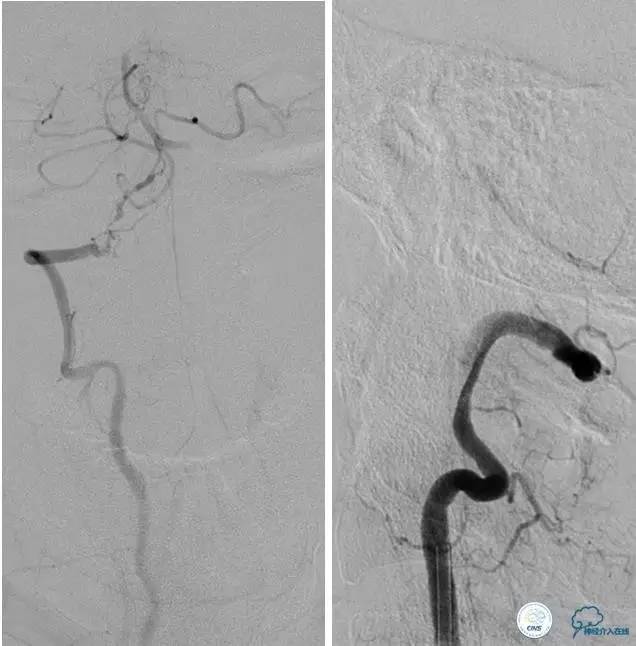

▼DSA示右侧椎动脉发育低下,弥漫性狭窄,可以看到左侧椎动脉反流,因此判断左侧椎动脉V4段CTO。

治疗:

微导丝穿过闭塞段,微导管造影,球扩闭塞段,置入Wingspan支架,血流完全恢复正常。

患者术后2天再次出现卒中发作,药物治疗好转,此后病情稳定。半年后复查DSA,见支架闭塞,侧支循环开放。患者一般情况好,mRS:1分。